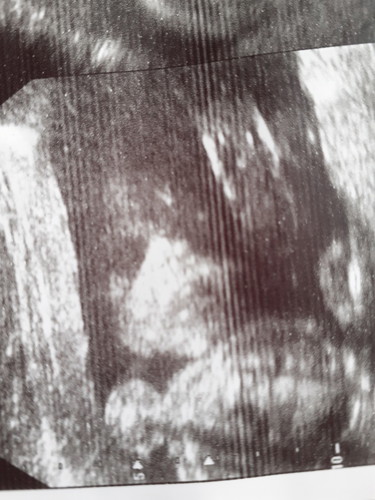

หลังจากมีเลือดออกทางช่องคลอด

ไปตรวจแล้วหมอบอกว่าน้องแข็งแรงปกติดีค่ะ 24wแล้วคร่าขอบคุนทุกคนนะค่ะที่ให้คำแนะนำ